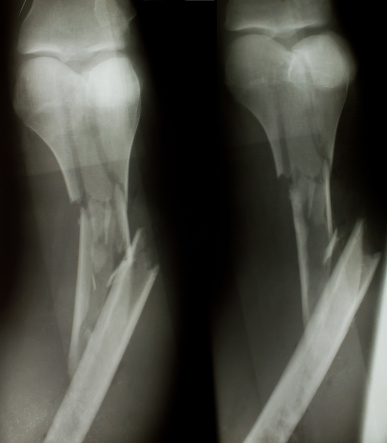

เมื่อเราประสบอุบัติเหตุต่างๆ จนทำให้กระดูกหัก การรักษาที่เราคุ้นเคยกันดี นั่นก็คือการใส่ เฝือก บางคนอาจจะเคยมีประสบการณ์การ การใส่เฝือกตั้งแต่ยังเด็ก เพราะมักจะเล่นซนจนทำให้กระดูก ขา แขน ร้าว แตกหรือหักได้ แน่นอนว่าการใส่ เฝือก สร้างความรำคาญให้แก่ผู้ป่วย ทำอะไรก็ไม่ถนัด จะอาบน้ำก็กลัวจะเปียก แถมบางทีก็คันยุบยิบข้างใน เฝือก ก็ไม่สามารถเกาได้ บางคนชอบเอาไม้แหย่เข้าไปเกา พฤติกรรมเหล่านี้ทำให้เกิดอาการติดเชื้อ และอักเสบได้ แทนที่กระดูดจะสมานต่อกันและหาย กลับต้องมารักษาอาการอักเสบพวกนี้อีก วันนี้เราเลยมีคำแนะนำสำหรับผู้ป่วยที่ใส่ เฝือก มาฝากกันค่ะ ว่าเราควรจะทำตัวยังไงเมื่อต้องใส่ เฝือก

คำแนะนำสำหรับผู้ป่วยที่ใส่ เฝือก

1. ยกแขนหรือขาส่วนที่ใส่ เฝือก ให้สูงกว่าระดับหัวใจ โดยเฉพาะใน 24 ชั่วโมงแรกเพื่อลดอาการบวม